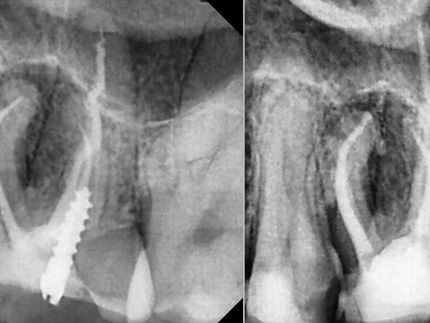

Endodontic treatment aims to repair and save a badly damaged infected tooth. the procedure involves removing the damaged pulp or nerve, cleaning disinfecting it, and then filling and sealing it.

The following cases were done using MTWO rotary endodontic instruments by VDW for fast and safe root canal preparation.